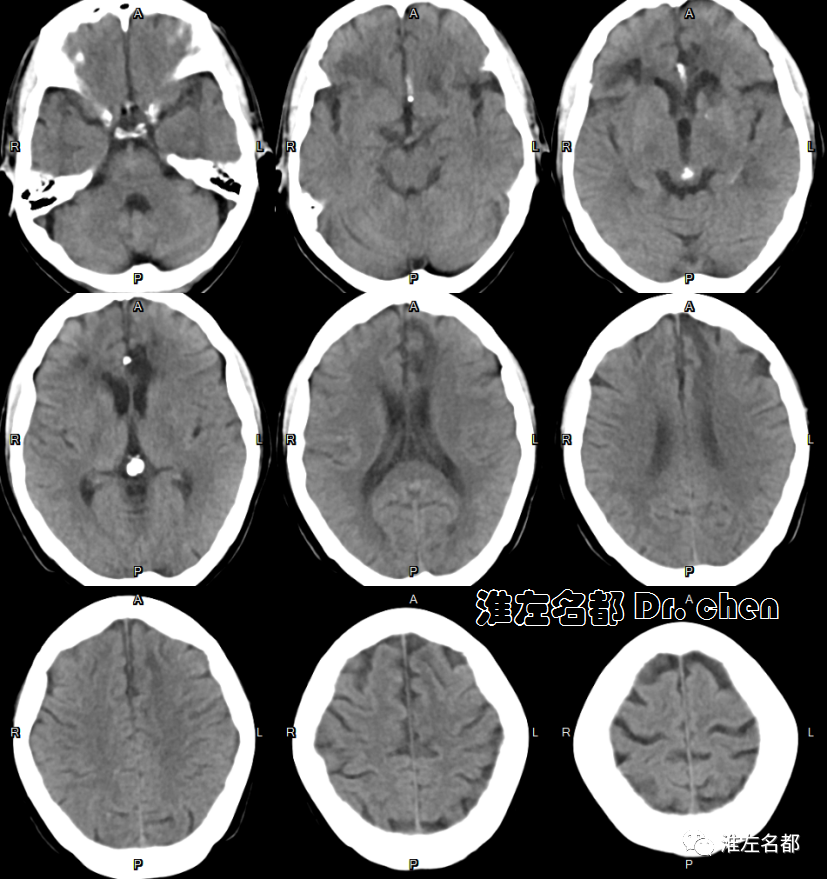

△头颅CT平扫:右侧额叶陈旧性梗死,左侧胼胝体膝部和临近脑组织低密度。

△颅脑CT平扫:左侧大脑前动脉支架(橙箭)植入术后;左侧尾状核头部、胼胝体膝部和临近额叶低密度梗死。

△颅脑CT平扫:左侧尾状核头部、胼胝体膝部和临近额叶陈旧性梗死,局部坏死液化;右侧额叶陈旧性梗死。